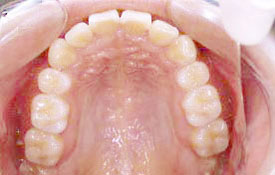

インビザラインの治療例:CASE-2

| プロフィール | 15歳 男性 |

| 所見 | アメリカから転院されて来られた方です。 インビザラインで上下顎の矯正治療を開始し下顎はアメリカで終了しており、上顎のみ治療の後期を担当しました。 アイライナーの装着は、1日平均22時間ほどでした。 |